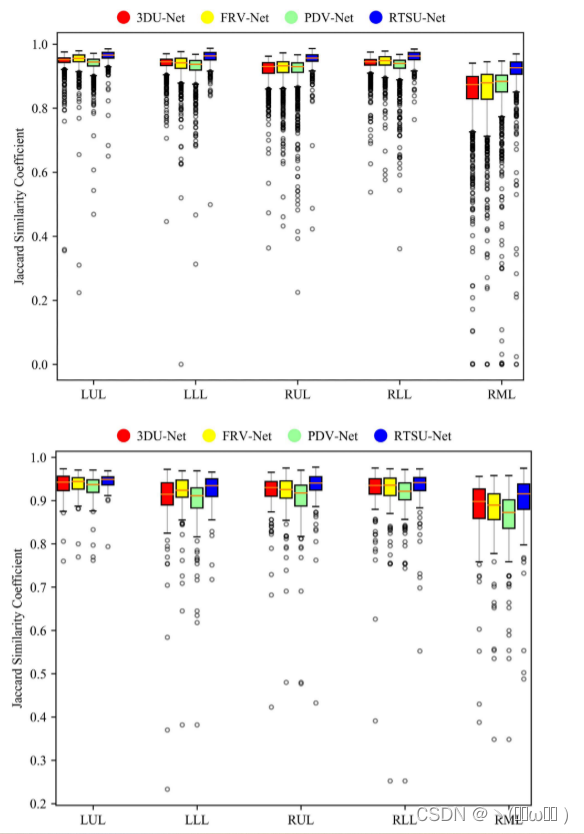

表 III 报告了两个数据集的定量结果。在所有测量中,所提出的方法在两个数据集(P < 0.01,Bonferroni 校正)上均显着优于基线方法和两种已发布的端到端叶分割方法。考虑到较小的标准偏差,我们的模型还表现出更稳健的性能。图 2 中提供了箱线图。这些图表明,对于 COVID-19 和 COPD 病例,右中叶是最难分割的,鉴于其已知的高度变化和形状差异,这不足为奇。事实上,小裂缝通常不完整甚至不存在。 RTSU-Net 在两个数据集上明显优于其他方法。还可以观察到,低 IOU 的异常值较少,表明 RTSU-Net 更健壮。

图 2:COPD数据集 (上) 和新型冠状病毒肺炎数据集 (下) 上不同方法的IOU每叶的箱形图和晶须图。